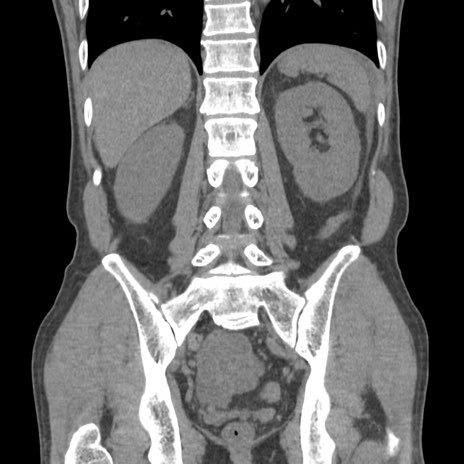

症例56 CT(冠状断像)

横断像